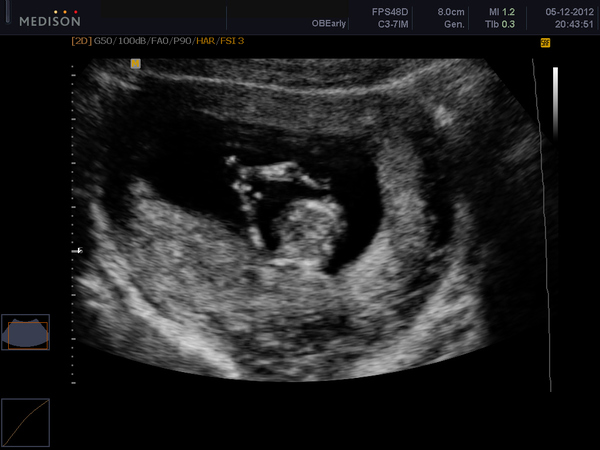

А малыш сначала был развернут к нам жопкой, но потом мы его разтормошили и он(она) сначала так сладенько смоктал пальчик, потом махал нам ручкой, ножками что-то там дрыгался, вобщем одно умиление. А вот и фотки: